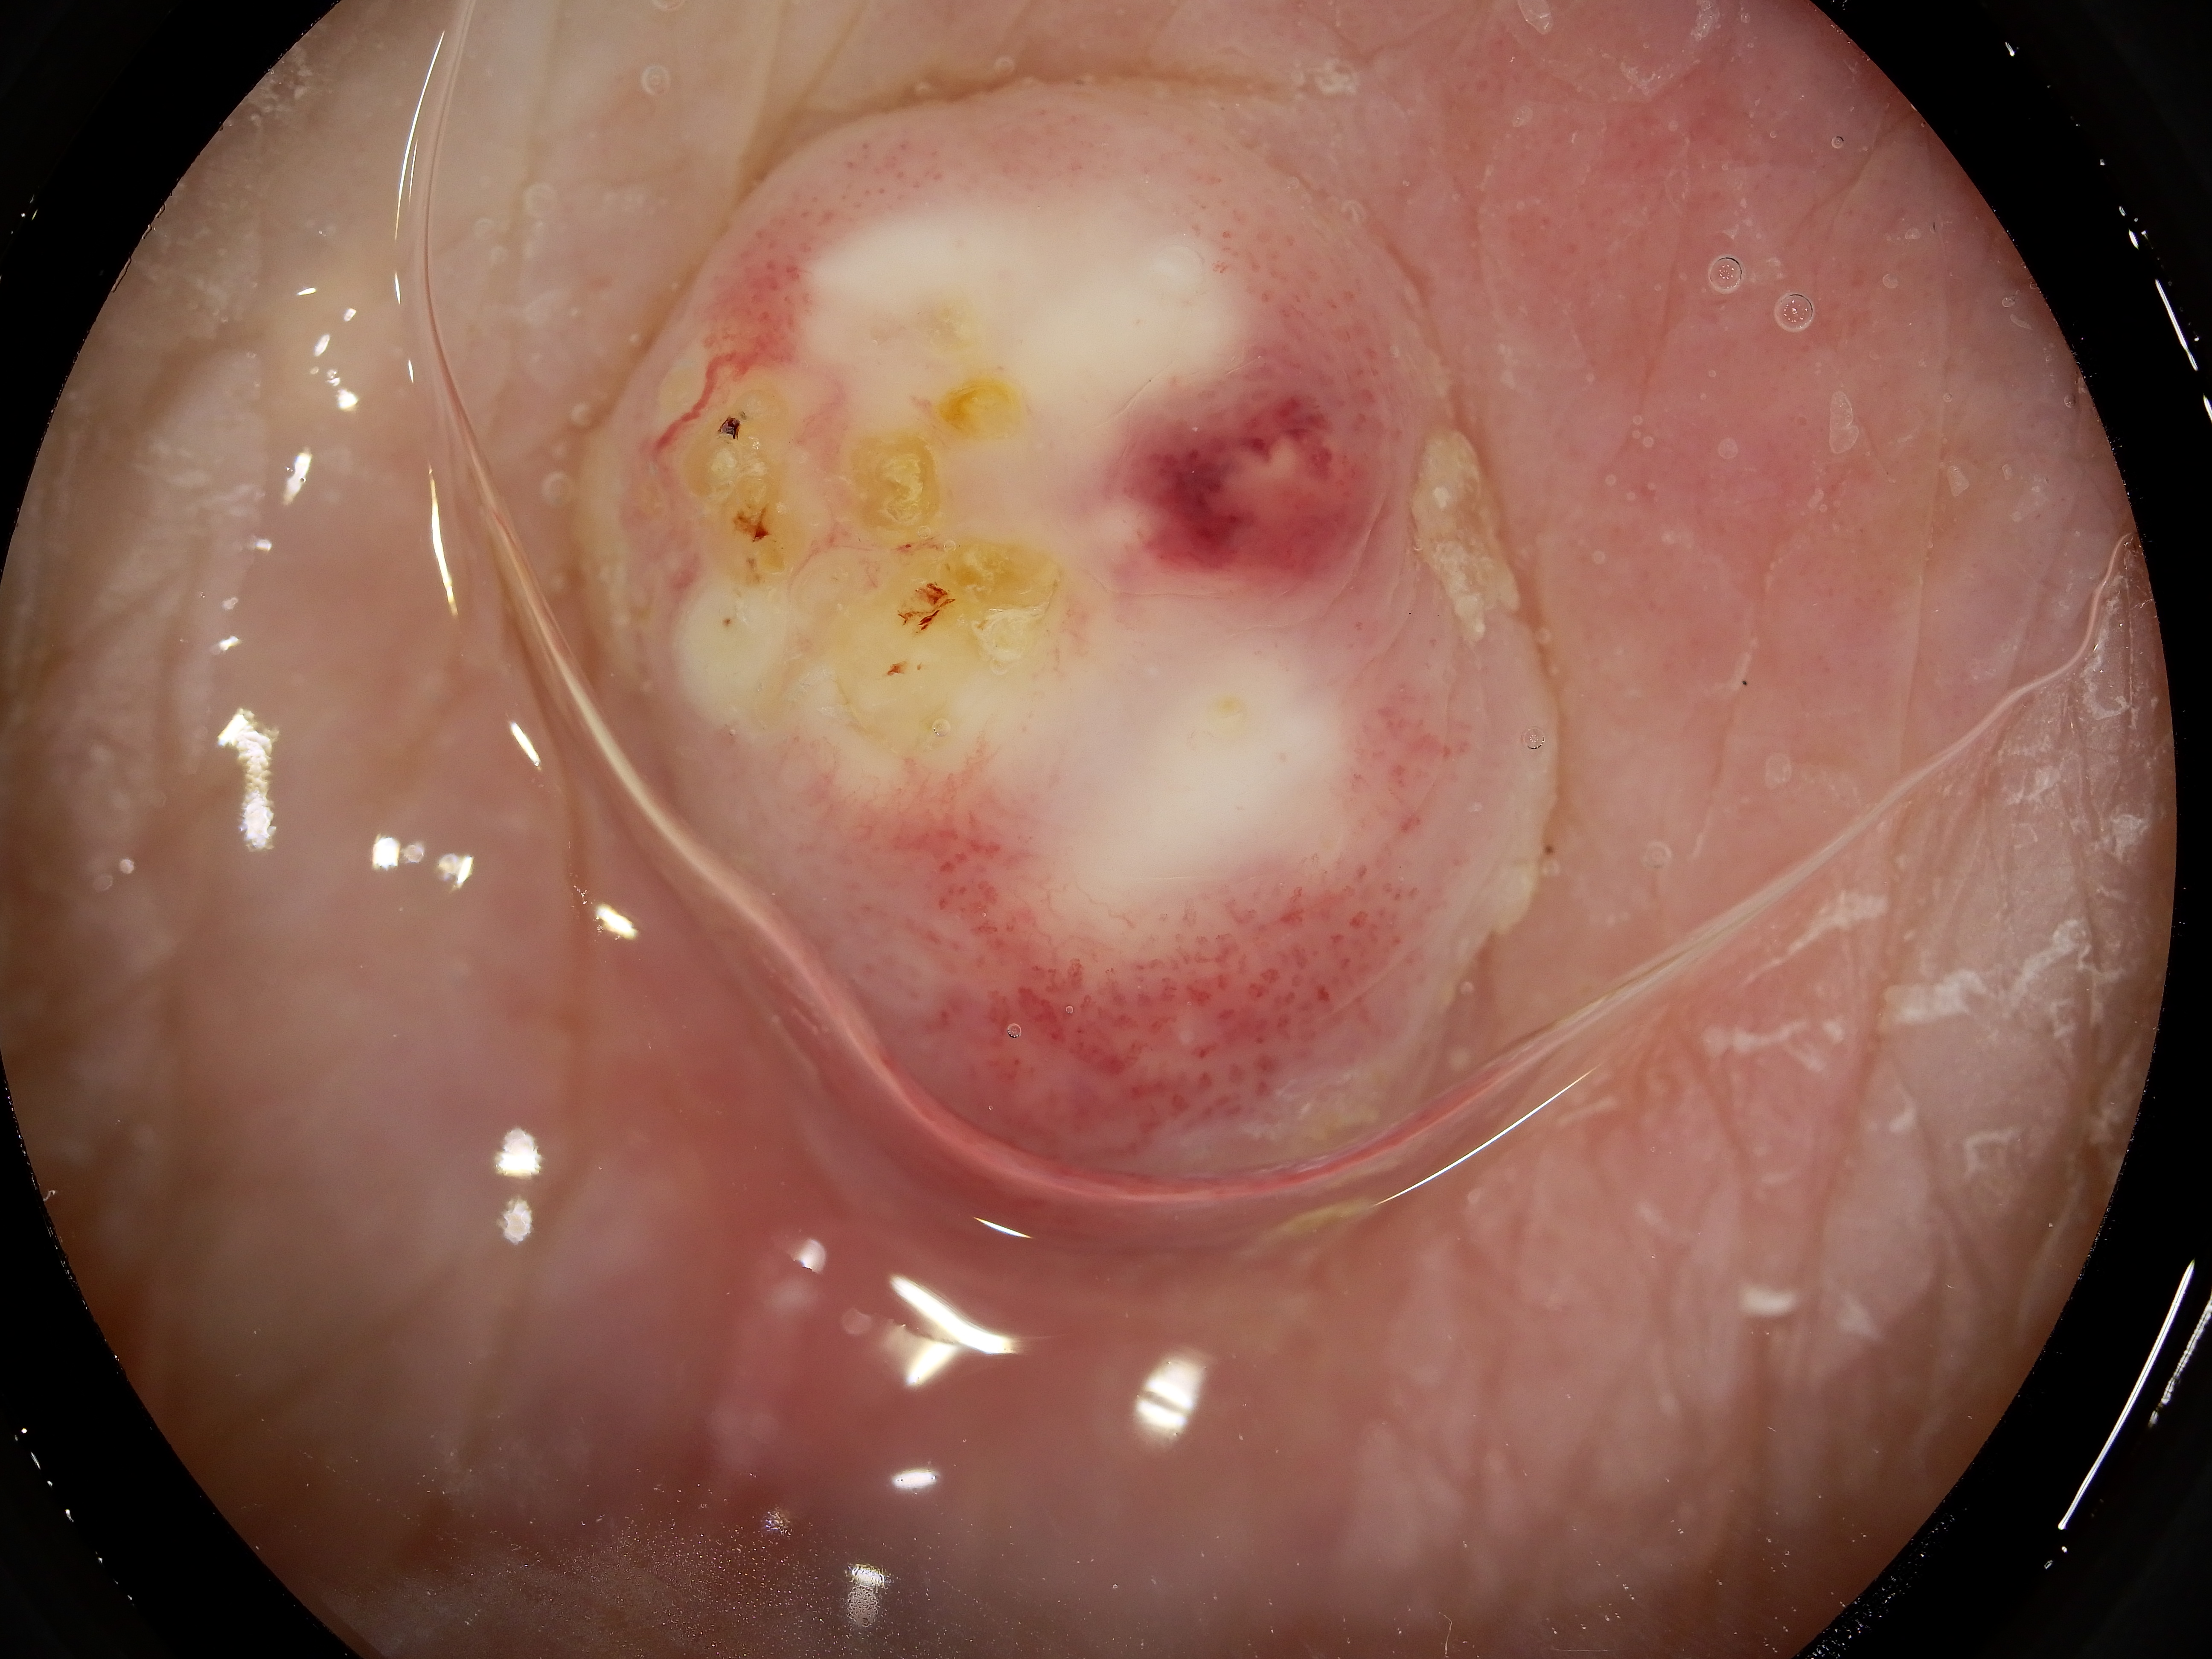

Site: Thigh

Diagnosis: Keratoacanthoma

Type: Dermlite Polarised

Description: Firm rapidly growing nodule on the thigh

This 99 years old lady developed this nodule on her thigh, It came up rapidly just after she ceaeased a Braf inhibitor drug for melanoma. It was reported as a keratoacanthoma. KAs and SCC like lesions are commonly seen in patients on Braf inhibitor drugs.

Dermatoscopy of SCCs and keratoacanthomas Dermatoscopy of solitary keratoacanthoma